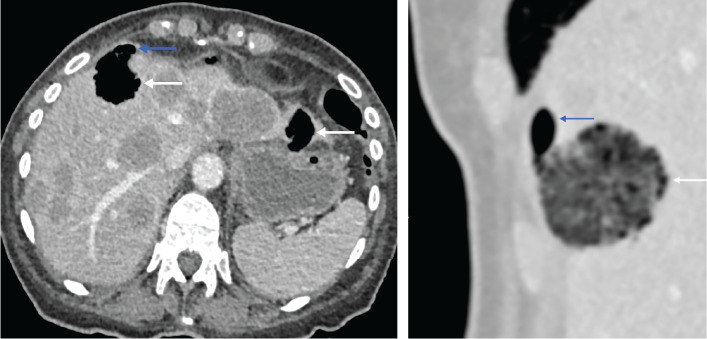

A rare case of hepatic gas-forming metastases secondary to Clostridium septicum infection is described. A 78-year-old woman was admitted with right lower quadrant abdominal pain and deterioration. Initial imaging revealed a right-sided colonic malignancy with hepatic metastases. Follow-up scans showed gas within metastases and minimal pneumoperitoneum, suggesting bowel perforation. However, blood cultures isolated C. septicum, supporting infected necrotic metastases as the source of free gas. Teaching point: This case emphasizes the importance of distinguishing infectious intratumoral gas from perforation in oncological patients and provides one of the few reports with sequential imaging of this process.